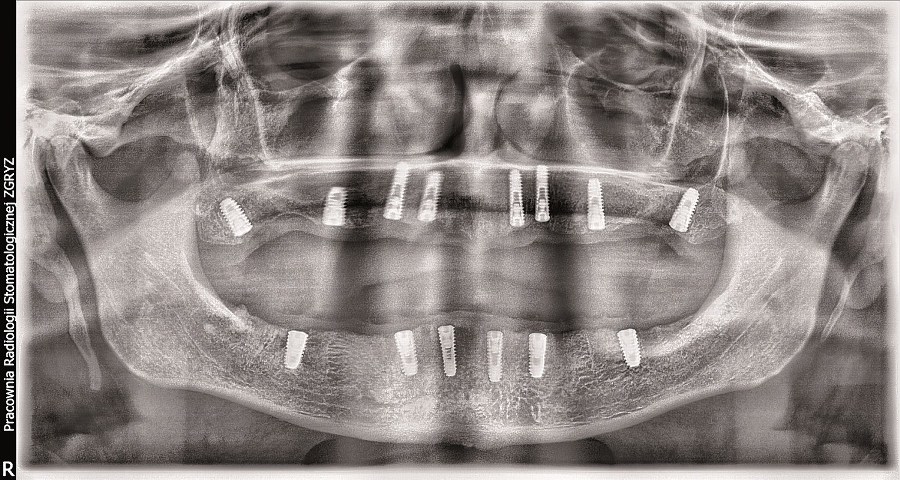

Dr Dariusz Srokowski: Implanty to rozwiązanie dla pacjentów mających braki w uzębieniu lub dotkniętych całkowitym bezzębiem, którzy spełniają określone warunki kostne. Decyzja o podjęciu i przebiegu leczenia zapada na podstawie wnikliwej analizy danych uzyskanych w badaniu pantomograficznym (zdjęcie panoramiczne) i tomograficznym (obrazowanie trójwymiarowe).

W mojej opinii, w naprawdę wyjątkowych przypadkach można umocować 12 zębów na stałe na 4 implantach. Warunki muszą być jednak bardzo sprzyjające. Aby wszczepić wystarczająco długie i szerokie implanty do utrzymania 12 zębów, kość musi być obfita. Bardziej realistyczną liczbą jest 5 do 8 implantów. Wówczas nie są one przeciążone, a siły zgryzu rozkładają się prawidłowo. Ostateczna ilość implantów przy pełnej rekonstrukcji to decyzja bardzo indywidualna i złożona. Składają się na nią  takie czynniki, jak jakość i ilość kości, tonacja mięśni twarzy, rozmiar szczęki i żuchwy pacjenta.

Pełna rekonstrukcja uzębienia jest jedną z najtrudniejszych procedur w stomatologii. Jeżeli odbudowa protetyczna uzębienia obejmuje także własne zęby pacjenta, to możemy wykorzystać korony, mosty i implanty występujące pojedynczo lub połączone w mosty. Pełną rekonstrukcję zaczynamy od wstępnej analizy jamy ustnej, modeli pacjenta stworzonych na podstawie wycisku, zdjęć rtg oraz tomografii. Na podstawie tych informacji wykonujemy projekt przyszłego uzębienia. Dalszy przebieg leczenia jest uzależniony od tego, jakie procedury należy wykonać, zanim możliwa będzie implantacja. Po wszczepieniu implantów następuje etap uzupełnień tymczasowych/próbnych, na podstawie których pacjent może ocenić estetykę i wygodę przyszłych uzupełnień stałych. Pacjent ma szansę zgłosić swoje uwagi do zaproponowanych uzupełnień stałych i uzyskać efekt końcowy, który go całkowicie ustatysfakcjonuje